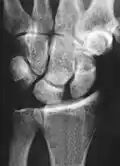

Scapholunate ligament disruption associated with a Colles' fracture